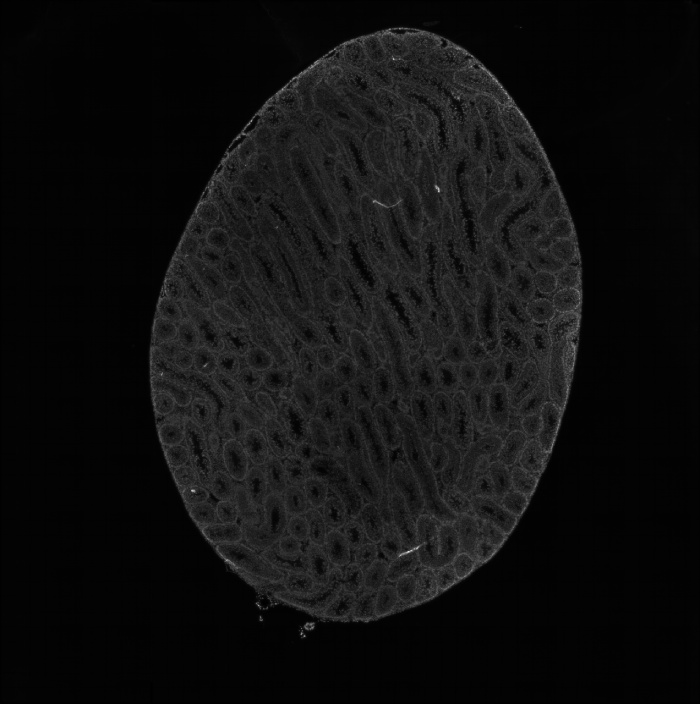

組織切片HE染色圖

圖1 組織切片HE染色圖